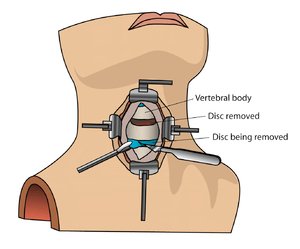

Cervical spinal fusion can be performed for several reasons. Following injury, this surgery can help stabilize the neck and prevent damage to the spinal cord. Additionally, cervical spinal fusion can be used to remove or reduce pressure on nerve roots caused by bone ingrowth osteophytes or herniated intervertebral disks.

Bone morphogenetic protein (rhBMP) should not be routinely used in any type of anterior cervical spine fusion, such as with anterior cervical discectomy and fusion.[2] There are reports of this therapy causing soft tissue swelling, which in turn can cause life-threatening complications due to difficulty swallowing and pressure on the respiratory tract.[2]

Interbody fusion places the bone graft between the vertebra in the area usually occupied by the intervertebral disc. In preparation for the spinal fusion, the disc is removed entirely, for example in ACDF. A device may be placed between the vertebra to maintain spine alignment and disc height. The intervertebral device may be made from either plastic or titanium. The fusion then occurs between the endplates of the vertebrae. Using both types of fusion is known as 360-degree fusion. Fusion rates are higher with interbody fusion. The types of interbody fusion are: